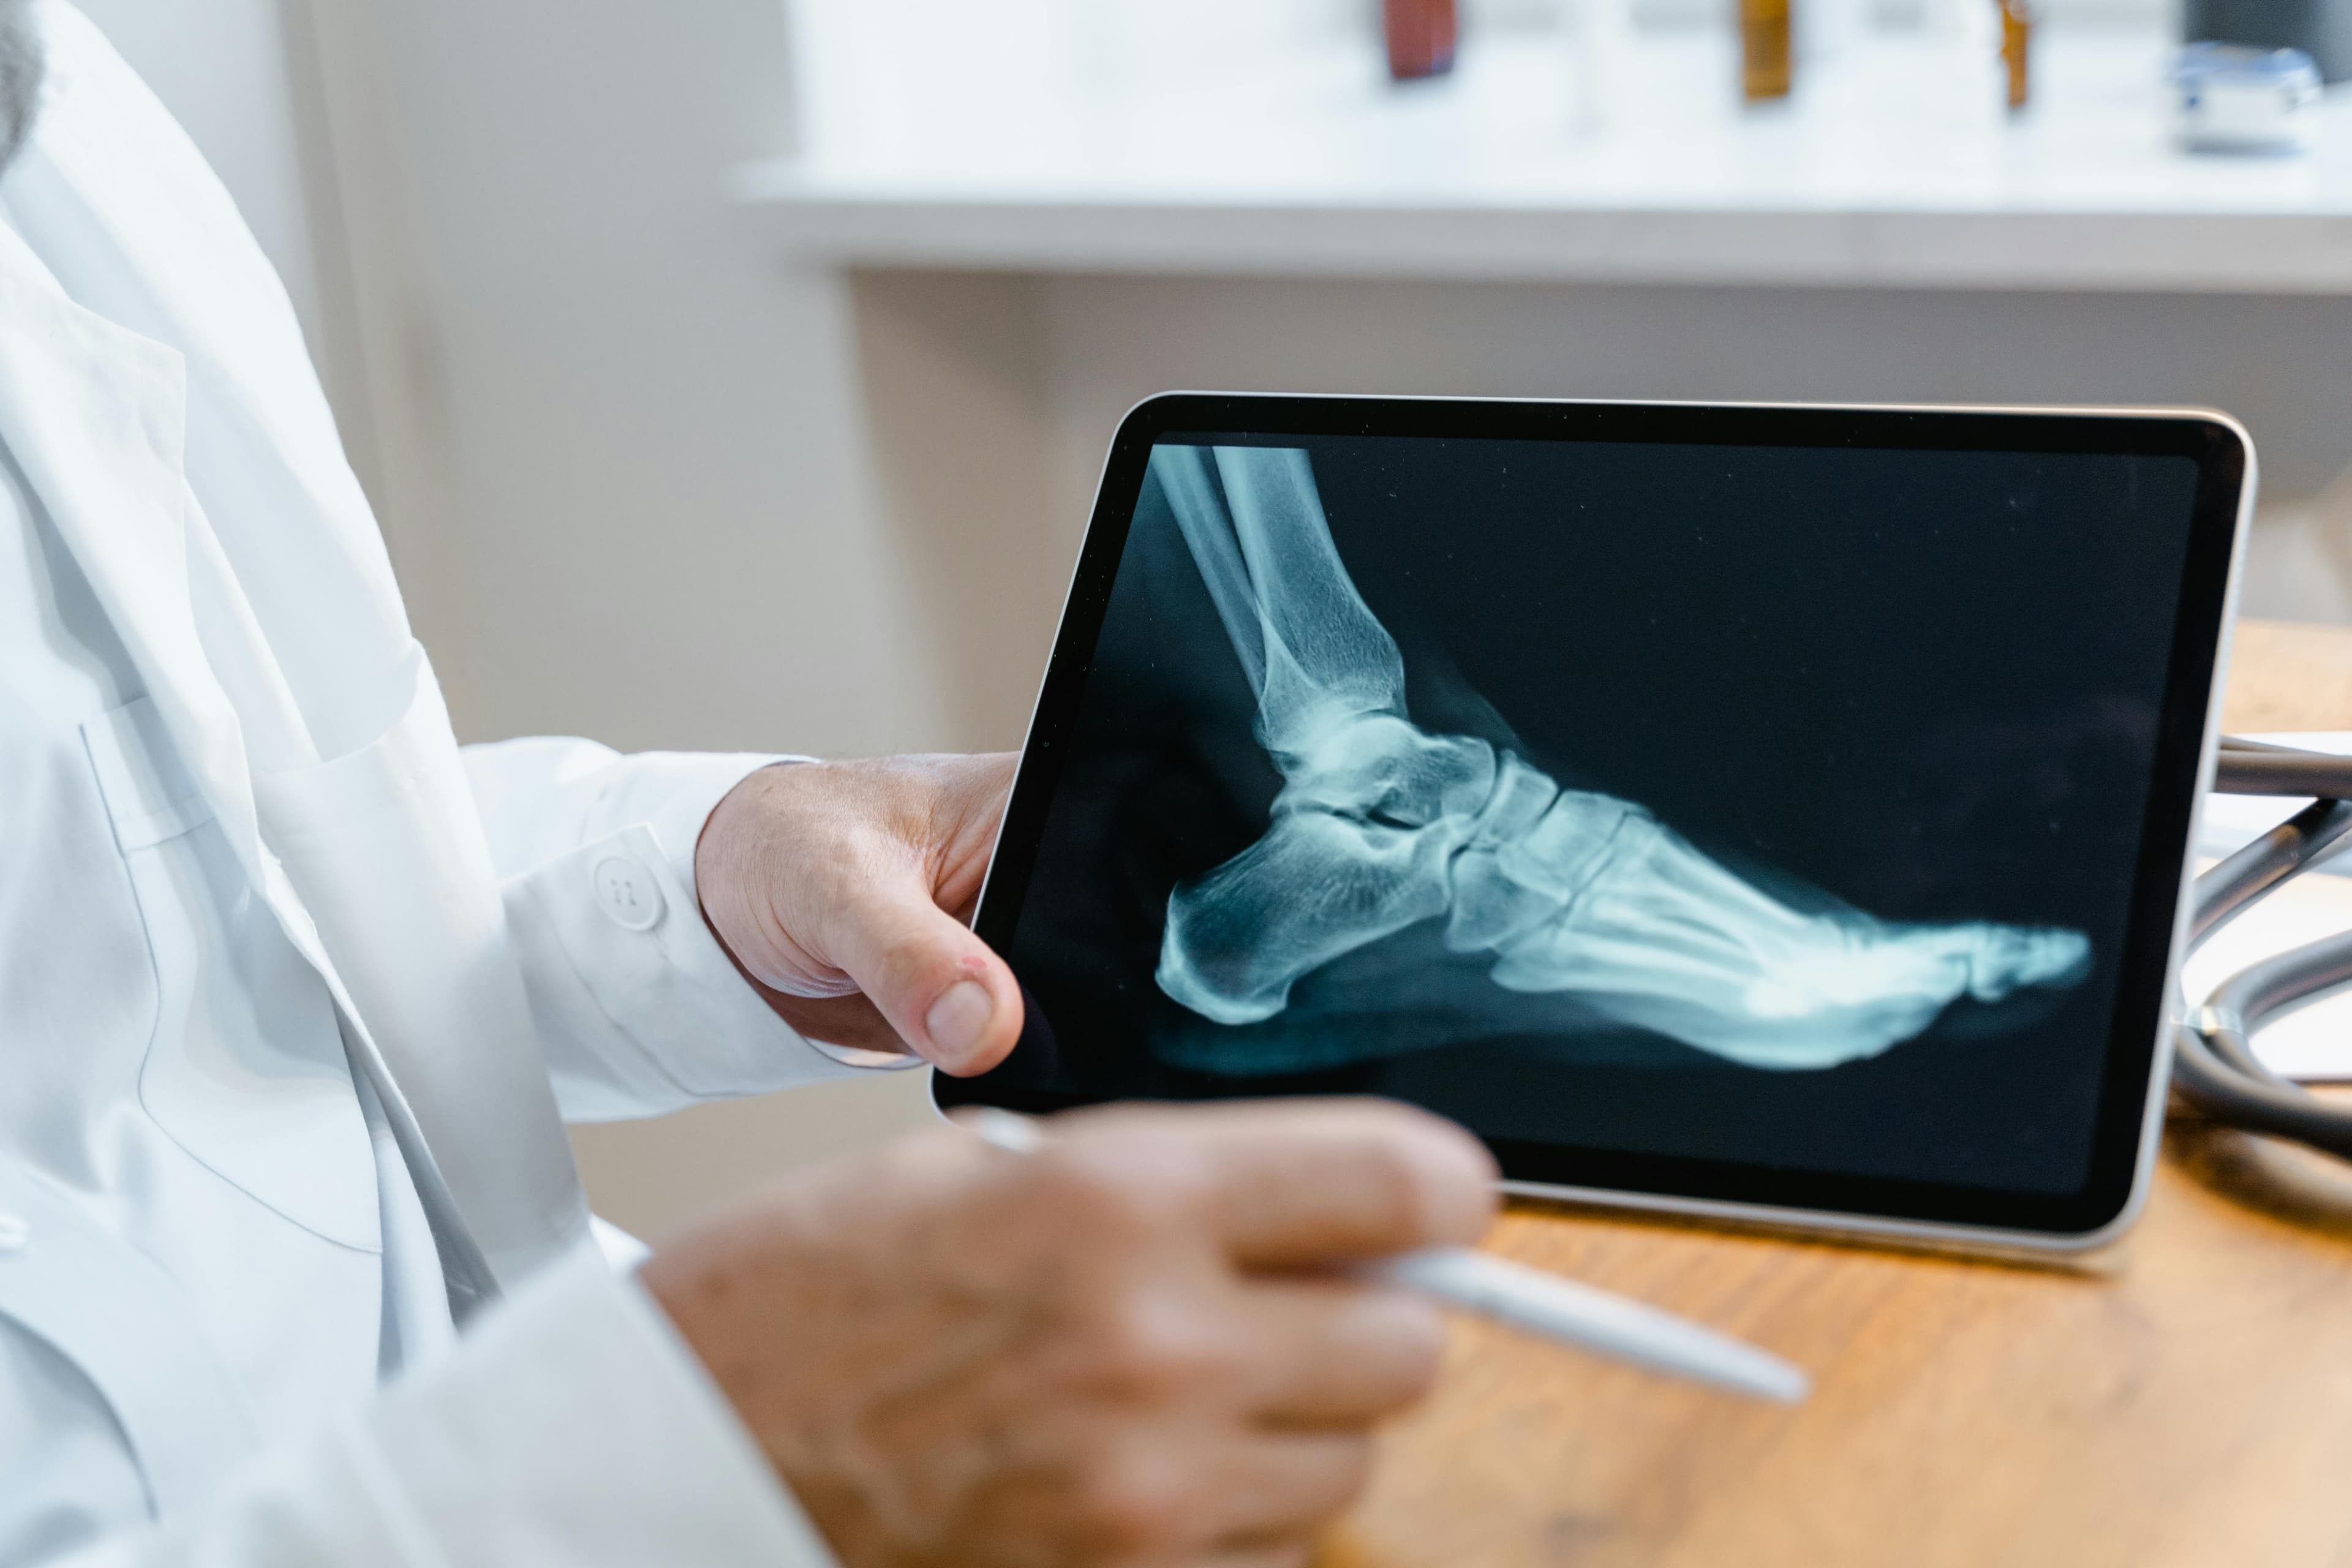

Warto pamiętać, że nie każdy ból stopy w śródstopiu lub okolicy pięty oznacza od razu obecność ostrogi piętowej, dlatego konieczne jest prawidłowe rozpoznanie oparte na wywiadzie, badaniu przedmiotowym i diagnostyce obrazowej (USG, RTG).